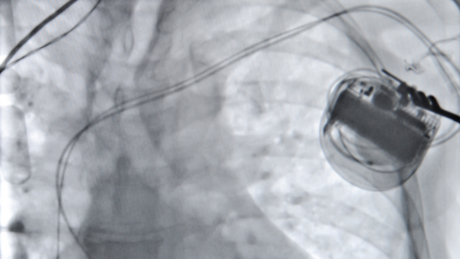

Schrittmacher und ICD

Der Herzschrittmacher kann verschiedenartige Störungen im elektrischen Leitsystem des Herzens beheben, in dem er bei einer Verlangsamung des Herzrhythmus oder bei vorübergehendem Stillstand einen elektrischen Impuls abgibt. Dieser bringt den Herzmuskel zum Schlagen und damit wieder in den richtigen Takt.

Der Defibrillator ist ein Herzschrittmacher und zusätzlich ein Gerät, das schnelle und gefährliche Herzrhythmusstörungen (Tachykardien) aus den Herzkammern einschließlich Kammerflimmern beenden kann. Dies erfolgt über eine schnelle Impulsabgabe an die Herzkammern oder - falls notwendig - auch durch einen Elektroschock (= Defibrillation).

Bei bradykarden Herzrhythmusstörungen (zu langsamer Herzschlag) kann je nach zugrundeliegender Herzrhythmusstörung ein sogenannter Ein- oder Zweikammer-Herzschrittmacher implantiert werden. Hierbei wird in örtlicher Betäubung beim Einkammergerät eine Sonde in die rechte Herzkammer gelegt, beim Zweikammergerät wird zusätzlich noch eine Sonde in den rechten Vorhof gelegt.

Bei tachykarden Herzrhythmusstörungen (zu schneller Herzschlag) kann bei bestimmten Indikationen durch die Implantation eines Kardioverter-Defibrillators (AICD. Oder umgangssprachlich „Defi“) das Risiko des plötzlichen Herztodes gesenkt werden. Auch hier stehen Ein-und Zweikammergeräte zur Verfügung.